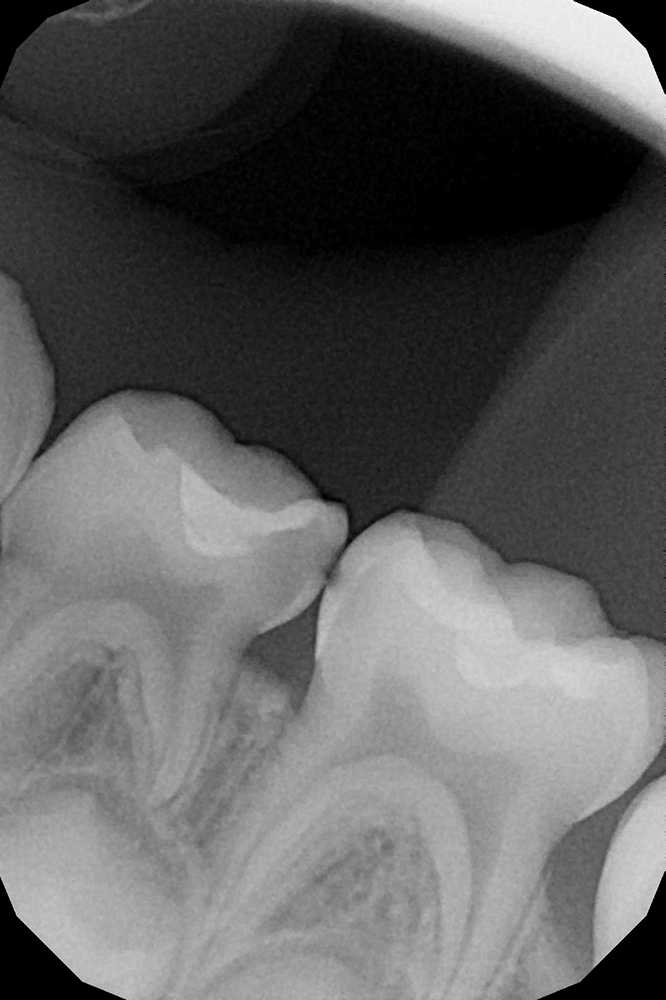

Сохранение зуба при обратимом пульпите